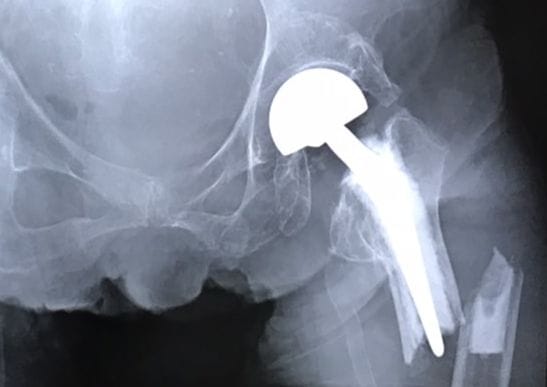

下の画像で、2回目の骨折の状況が分かります。

白く映っているのが、2014年の1回目の骨折で手術した人工骨頭及び繋いだ部分。

その下の先端の右に、細く亀裂があるのが2回目の骨折部位です。

しかし、退院後しばらくして12月12日に、骨折部分が、太股に突き出してきて、外に飛び出す心配があるので、急性期病院に予約してあるので行くよう再度要請。

急ぎ翌日、介護タクシーで病院へ行き、レントゲン撮影。

その画像が以下です。

骨折部分が、外に向かって突出。

これが大きなコブのように、太ももから盛り上がり、痛々しい状態に変化していました。